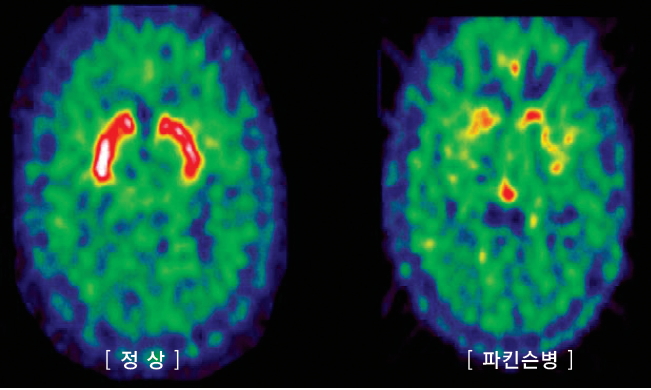

대표적인 퇴행성 뇌 질환인 파킨슨병은 중간 쪽 뇌에 위치해 있는 흑질이라는 뇌의 특정부위에서 도파민을 분비하는 신경세포가 원인을 알 수 없이 점점 사라져 가는 질환으로 서동증과 안정 시 떨림, 근육 강직, 자세의 불안정과 같은 증상들이 나타나게 됩니다. 따라서 이 세포들이 어떠한 이유로 죽게 되는지 그 이유에 대해서는 많은 연구가 진행 중이나 아직 확실한 결론을 얻지는 못하고 있는 실정이라고 합니다. 그리고 이 원인이 되는 뇌신경세포는 미상핵과 피각으로 불리는 두 부위로 신경섬유를 연결하고 있는데 대뇌 안에 깊게 위치하고 있다고 합니다.

파킨슨 병이 진단 방법은 환자를 직접 보고 관찰 후 임상적인 진단을 하는 것이 대표적인 방법입니다. 하지만 꼭 MRI 찍어야 되는 경우도 있게 되는데요. 그 이유는 "비전형적인 파킨슨증"과 "수두증" 혹은 "2차적인 파킨슨증" 외 철분 침착과 같은 증상이 있는지 또는 뇌에서 특징적인 뇌 취축 증상이 있는지 확인하기 위함으로 MRI 찍는 경우도 있습니다.